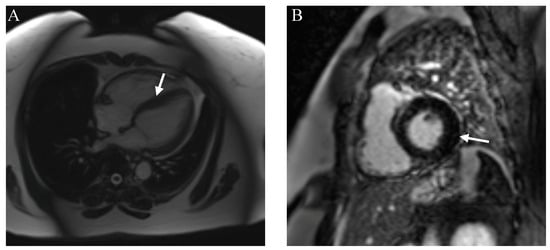

- Marschner, C.A.; Aloufi, F.; Aitken, M.; Cheung, E.; Thavendiranathan, P.; Iwanochko, R.M.; Balter, M.; Moayedi, Y.; Duero Posada, J.; Hanneman, K. Combined FDG PET/MRI versus Standard-of-Care Imaging in the Evaluation of Cardiac Sarcoidosis. Radiol. Cardiothorac. Imaging 2023, 5, e220292. [Google Scholar] [CrossRef]

- Kurashima, S.; Kitai, T.; Xanthopoulos, A.; Skoularigis, J.; Triposkiadis, F.; Izumi, C. Diagnosis of cardiac sarcoidosis: Histological evidence vs. imaging. Expert. Rev. Cardiovasc. Ther. 2023, 21, 693–702. [Google Scholar] [CrossRef]

- Hervier, E.; Glessgen, C.; Nkoulou, R.; François Deux, J.; Vallee, J.P.; Adamopoulos, D. Hybrid PET/MR in Cardiac Imaging. Magn. Reson. Imaging Clin. N. Am. 2023, 31, 613–624. [Google Scholar] [CrossRef]

- Shrivastav, R.; Hajra, A.; Krishnan, S.; Bandyopadhyay, D.; Ranjan, P.; Fuisz, A. Evaluation and Management of Cardiac Sarcoidosis with Advanced Imaging. Heart Fail. Clin. 2023, 19, 475–489. [Google Scholar] [CrossRef]

- Puntmann, V.O.; Isted, A.; Hinojar, R.; Foote, L.; Carr-White, G.; Nagel, E. T1 and T2 Mapping in Recognition of Early Cardiac Involvement in Systemic Sarcoidosis. Radiology 2017, 285, 63–72. [Google Scholar] [CrossRef]

- Dweck, M.R.; Abgral, R.; Trivieri, M.G.; Robson, P.M.; Karakatsanis, N.; Mani, V.; Palmisano, A.; Miller, M.A.; Lala, A.; Chang, H.L.; et al. Hybrid Magnetic Resonance Imaging and Positron Emission Tomography with Fluorodeoxyglucose to Diagnose Active Cardiac Sarcoidosis. JACC Cardiovasc. Imaging 2018, 11, 94–107. [Google Scholar] [CrossRef]

- Pöyhönen, P.; Nordenswan, H.K.; Lehtonen, J.; Syväranta, S.; Shenoy, C.; Kupari, M. Cardiac magnetic resonance in giant cell myocarditis: A matched comparison with cardiac sarcoidosis. Eur. Heart J. Cardiovasc. Imaging 2023, 24, 404–412. [Google Scholar] [CrossRef]